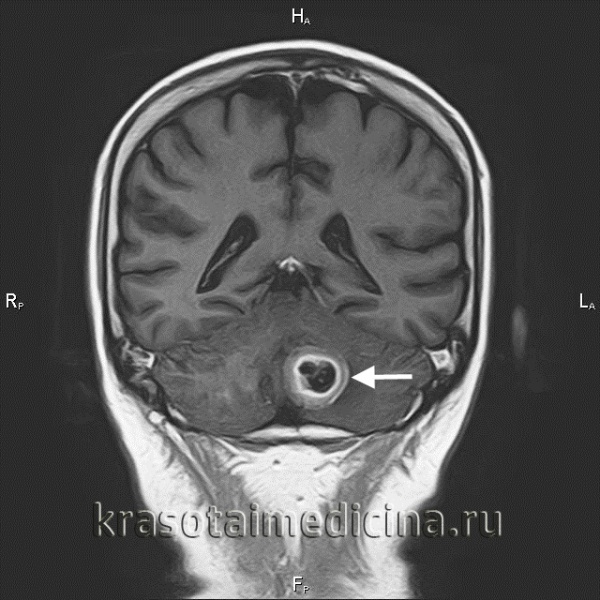

Менингеальный карциноматоз у пациента с доказанным метастазом бронхиальной аденокарциномы. Кистозный, с центральной гиподенсной зоной метастаз рака молочной железы, который может быть принят за глиобластому.. Метахронные метастазы колоректального рака с сопутствующими крупными и мелкими очагами. Аденокарцинома легких с кистозным симптоматическим метастазом в правой височной доле, выявленным на КТ (вверху слева), а также МРТ (вверху справа).

Инфратенториальный очаг гораздо лучше визуализируется на МРТ. Метастаз в пинеальную область с угрожающей окклюзионной гидроцефалией

и компрессией четверохолмной пластинки, который может быть легко резецирован. Диффузное поражение, которые не оставляет терапевтической возможности.